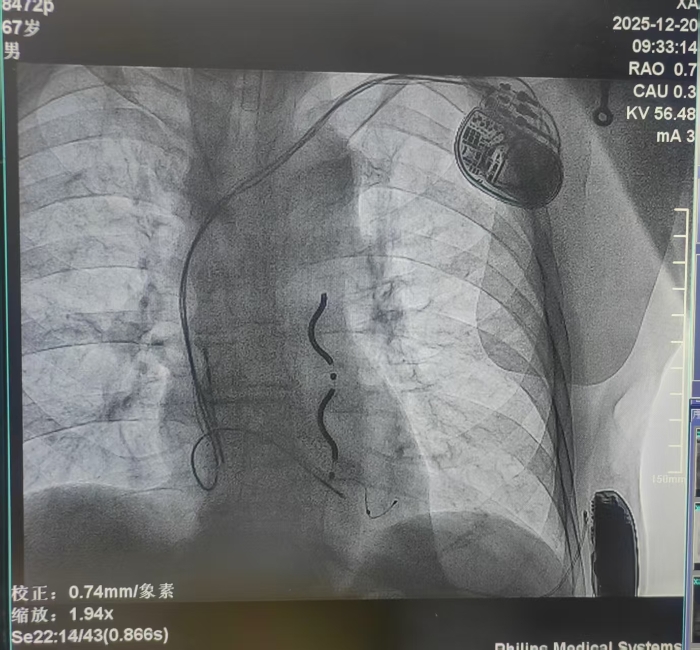

本例患者为67岁男性,7年前因患扩张型心肌病致心衰植入三腔起搏器(CRT-P),本次因室速晕厥入院,为心源性猝死的二级预防患者,需升级原起搏器为带有除颤功能的三腔起搏器(CRT-D)。但因患者上腔静脉闭锁,前期术中经多次尝试均无法经静脉植入除颤电极,为预防因恶性心律失常-室速、室颤导致患者晕厥及猝死,刘丽宏教授团队结合患者病情充分与患者及家属沟通后,为其选择植入EV-ICD血管外除颤器。团队在术前全面评估了原三腔起搏器的起搏感知功能良好,均为双极起搏状态;通过胸部CT认真评估患者解剖结构,审慎规划电极植入路径,并与心外科周钰峰主任及麻醉医师共同讨论手术操作细节,对术中可能遇到的问题进行了充分的讨论和准备,为患者制定了完善的手术方案。

△术中

胸骨下电极稳定,电学参数正常,原三腔起搏器工作状态未对EV-ICD的诊断治疗造成干扰,除颤测试通过,并同台更换了即将电池耗竭的原CRT-P起搏器。患者于手术次日由监护室转回普通病房即可下床活动,优化各项参数,患者恢复良好。